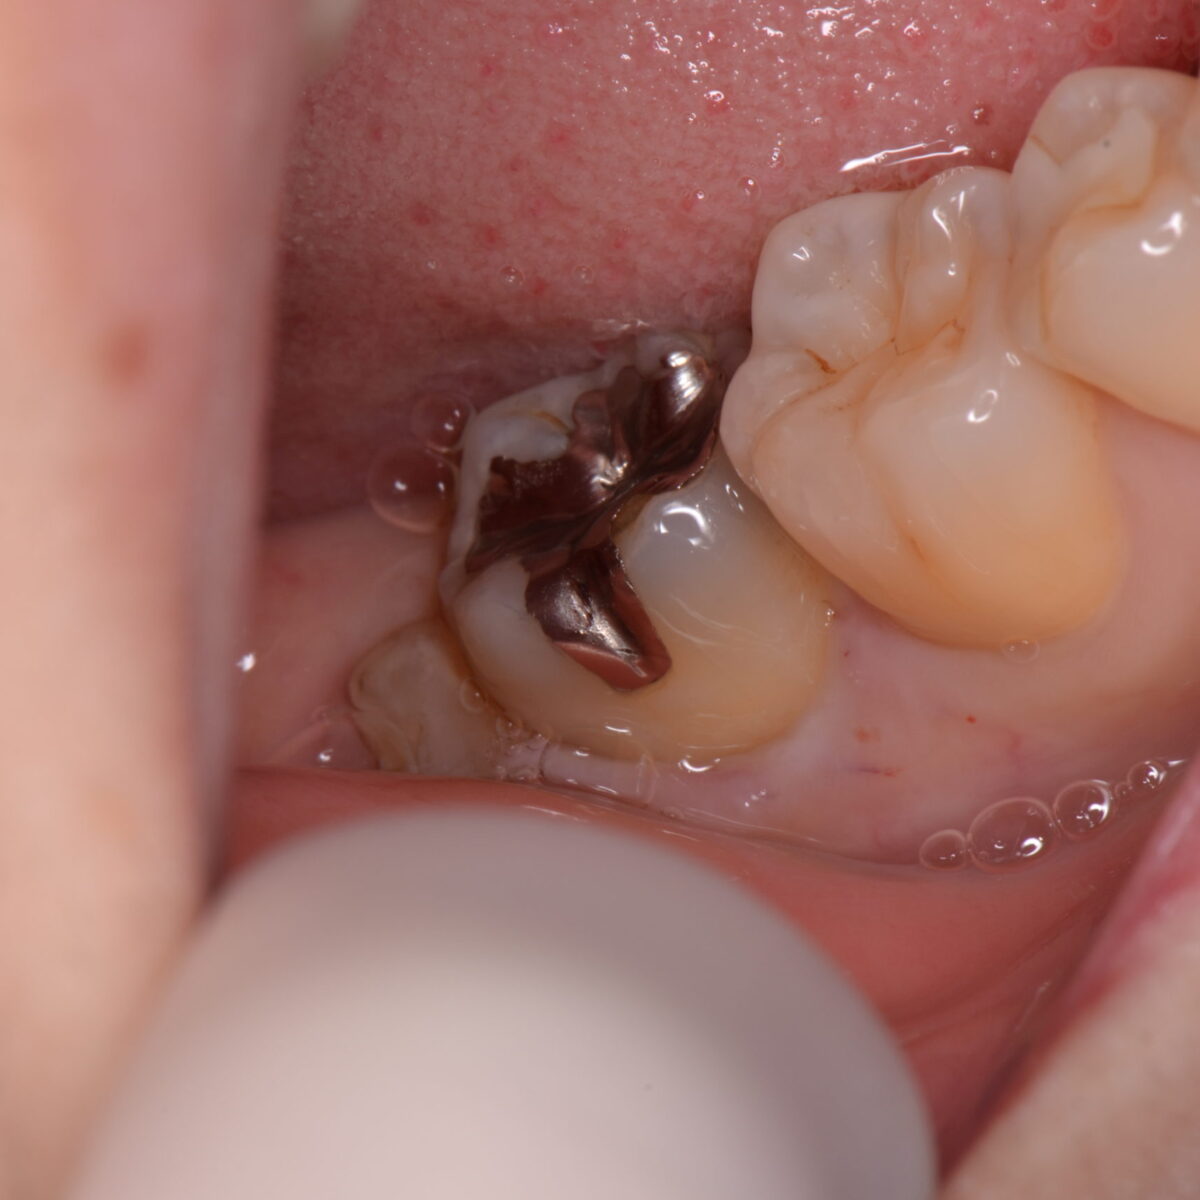

銀歯の下には・・・

【東京メトロ東西線妙典駅 徒歩5分の歯医者】市川、妙典の歯科医院、めぐりデンタルクリニックの梶原です。 今日は、銀歯の下がどうなっているかを載せます。 こちらにも同様のことを書いて…